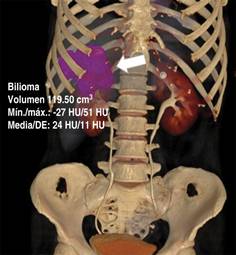

Figura 3: Reconstrucción VR3D con plataforma Syngo.vía de Siemens en la cual se cuantifica bilioma (flecha) con un volumen de 119.5 ml.